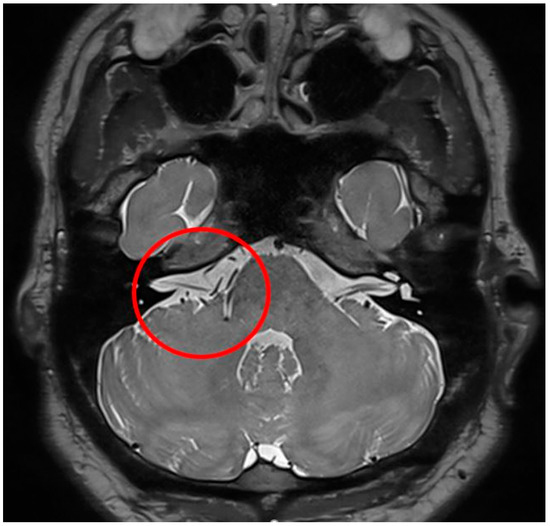

| 6 | AICA | Decline amplitude, but not disappeared | 50% decreased, delay to 1.6 ms, full recovery | 0 | 0 | 0 | N/A | None | On the lateral side, the AICA circled between CNs 7 and 8, penetrated the facial nerve medially, and exited laterally. |